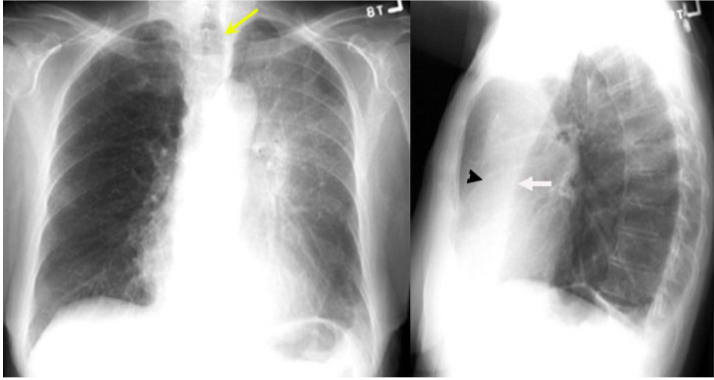

What type of atelectasis is this?

Resorptive of the LUL

What is the Luftsichel sign?

The lower lobe creeps up all the way up to the apical region